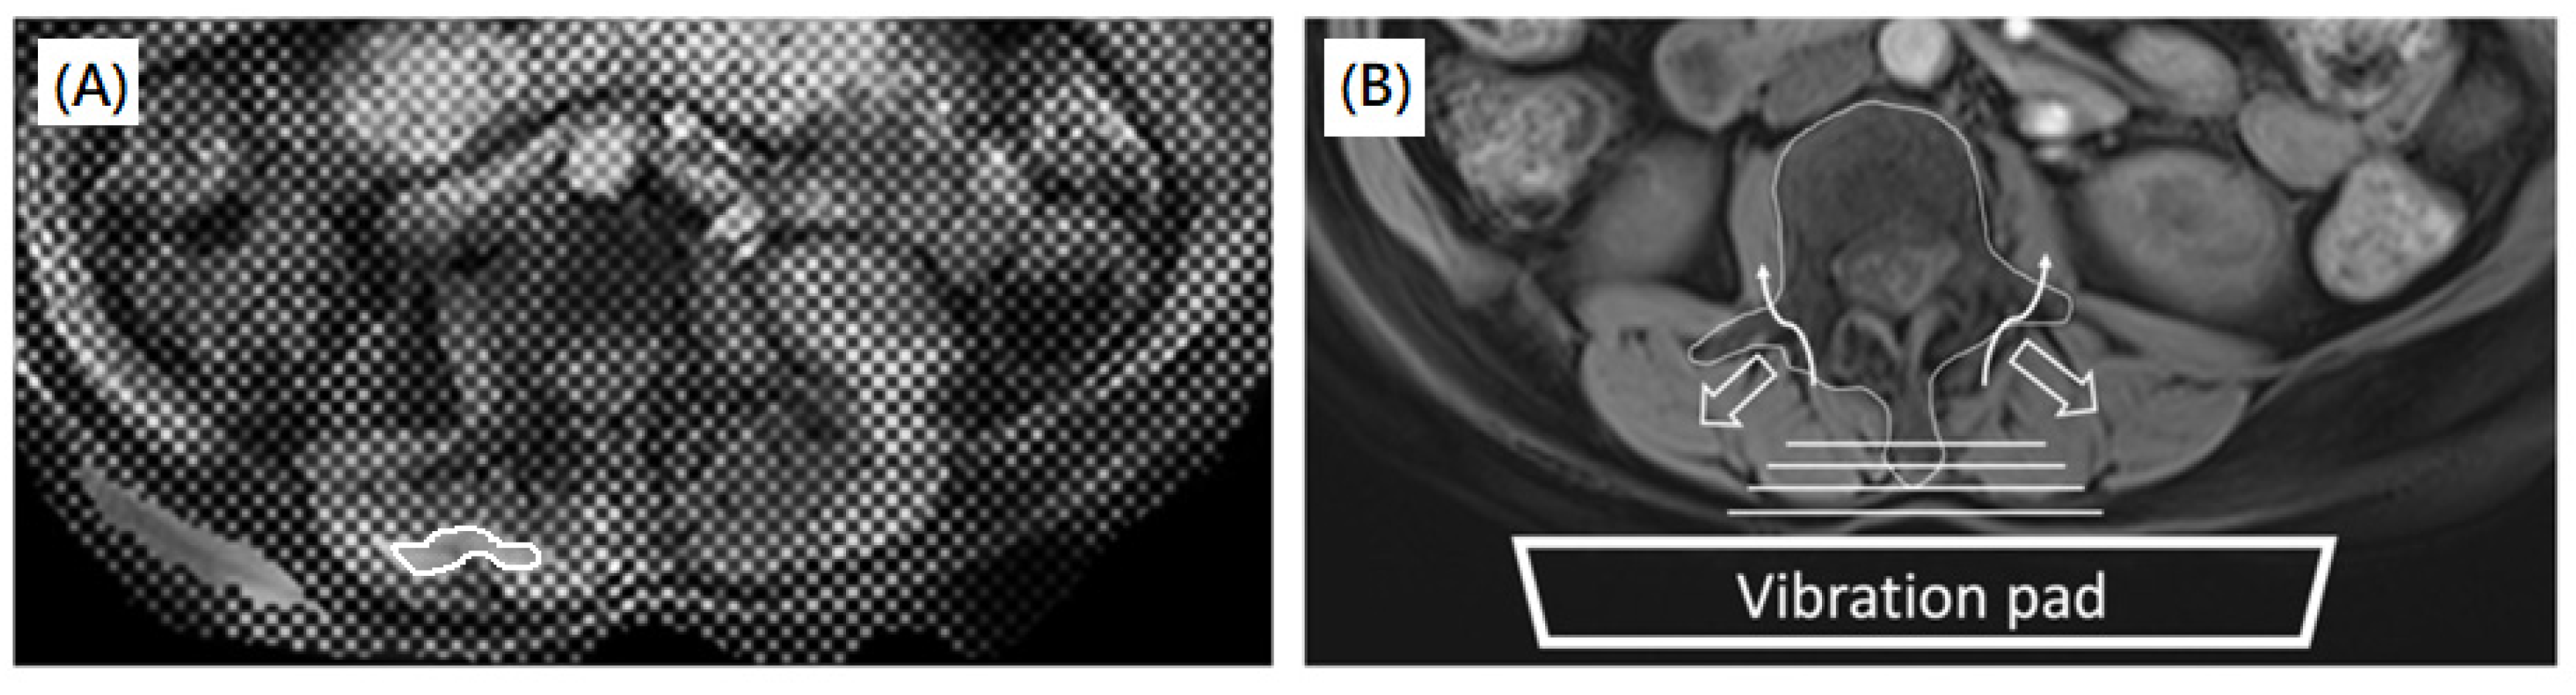

2.3. MRI Acquisition